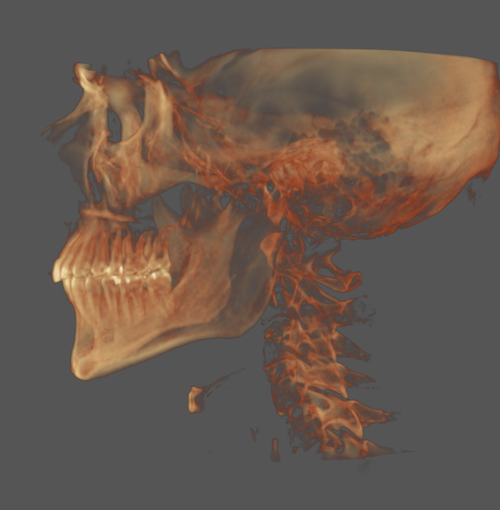

Planning on SARPE soon, too old for most ORTHO to work unfortunately.

Obviously leaning out which i am in the progress of but other than that not sure what else I can do or what my weakest features are. (My mandible is obviously recessed as is my maxilla.)